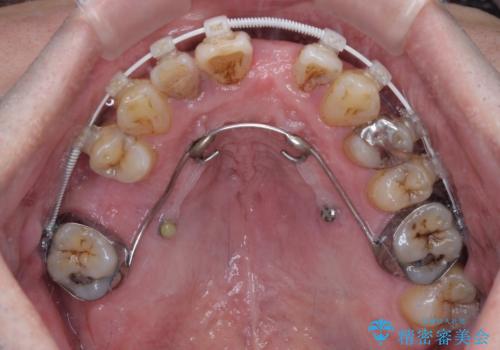

矯正治療を行いながら、欠損部はインプラントによる補綴治療を希望されたため、補助装置を用いたワイヤー矯正によりスペースを確保しながら歯列を整え、適宜インプラントを埋入していくこととしました。

上顎前歯もインプラントを希望していらっしゃいましたが、両隣の歯根が近接しており、インプラントは困難と判断したためオールセラミックブリッジによる補綴治療を前提として治療を開始することとしました。

在宅勤務のため、前歯にスペースが長期間できることに対して特に問題はないとおっしゃったため、スペースはそのままに治療を進めていくこととしました。